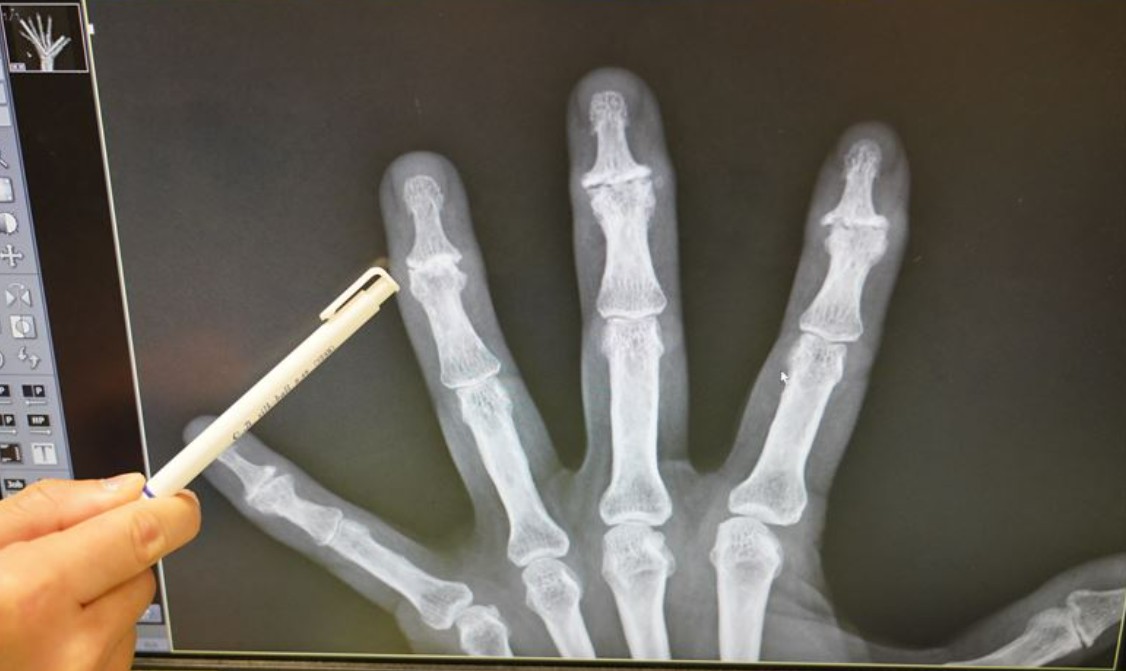

【本報訊】很多人誤以為手指關節變形就是類風濕性關節炎,其實在年紀大的患者造成手指關節變形更常見的原因,是手部退化性關節炎。手指退化性關節產生的原因是多面向的,常見因子有遺傳、女性、年長者、更年期後、肥胖、工作反覆勞動手指關節。

全身上下的關節都有罹患退化性關節炎的機會。除了膝關節、髖關節退化外,手部的退化性關節炎也很常見,尤其以手指的遠端指間關節和大拇指的掌指關節、掌腕關節最常發生。

手指疼痛最常發生在天氣濕冷、關節活動時,病況嚴重時可能會有關節局部發炎出現紅熱腫,變形後會出現關節活動困難。 在手部退化性關節炎中,有一部份患者特別嚴重,且惡化較快,容易造成關節變形與侵蝕,又稱為侵蝕性手部退化性關節炎。退化性關節炎沒有辦法根治,要讓手部有適當的休息,適時熱敷、按摩等,一旦感覺關節疼痛,就應該立即休息。